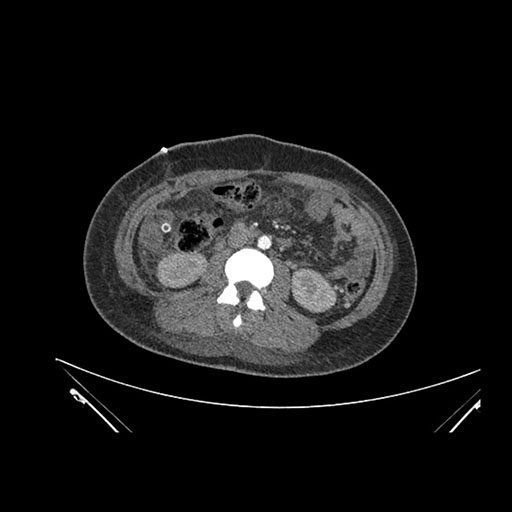

Axial Venous

Imaging analysis

Based on initial findings, which issue(s) would you be most concerned about?